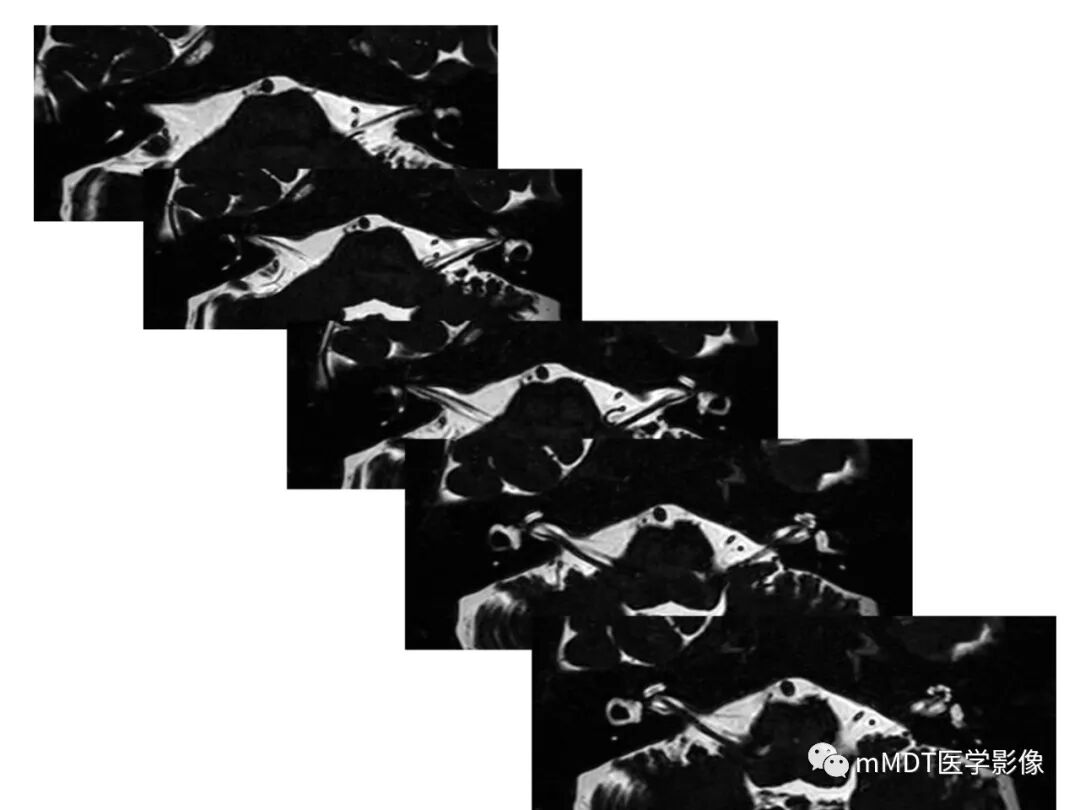

内耳道(internalacoustic meatus)位于颞骨岩部后面中部,自内耳门到内耳道底,内有前庭上神经前庭下神经蜗听神经面神经穿行(触底四神共一门